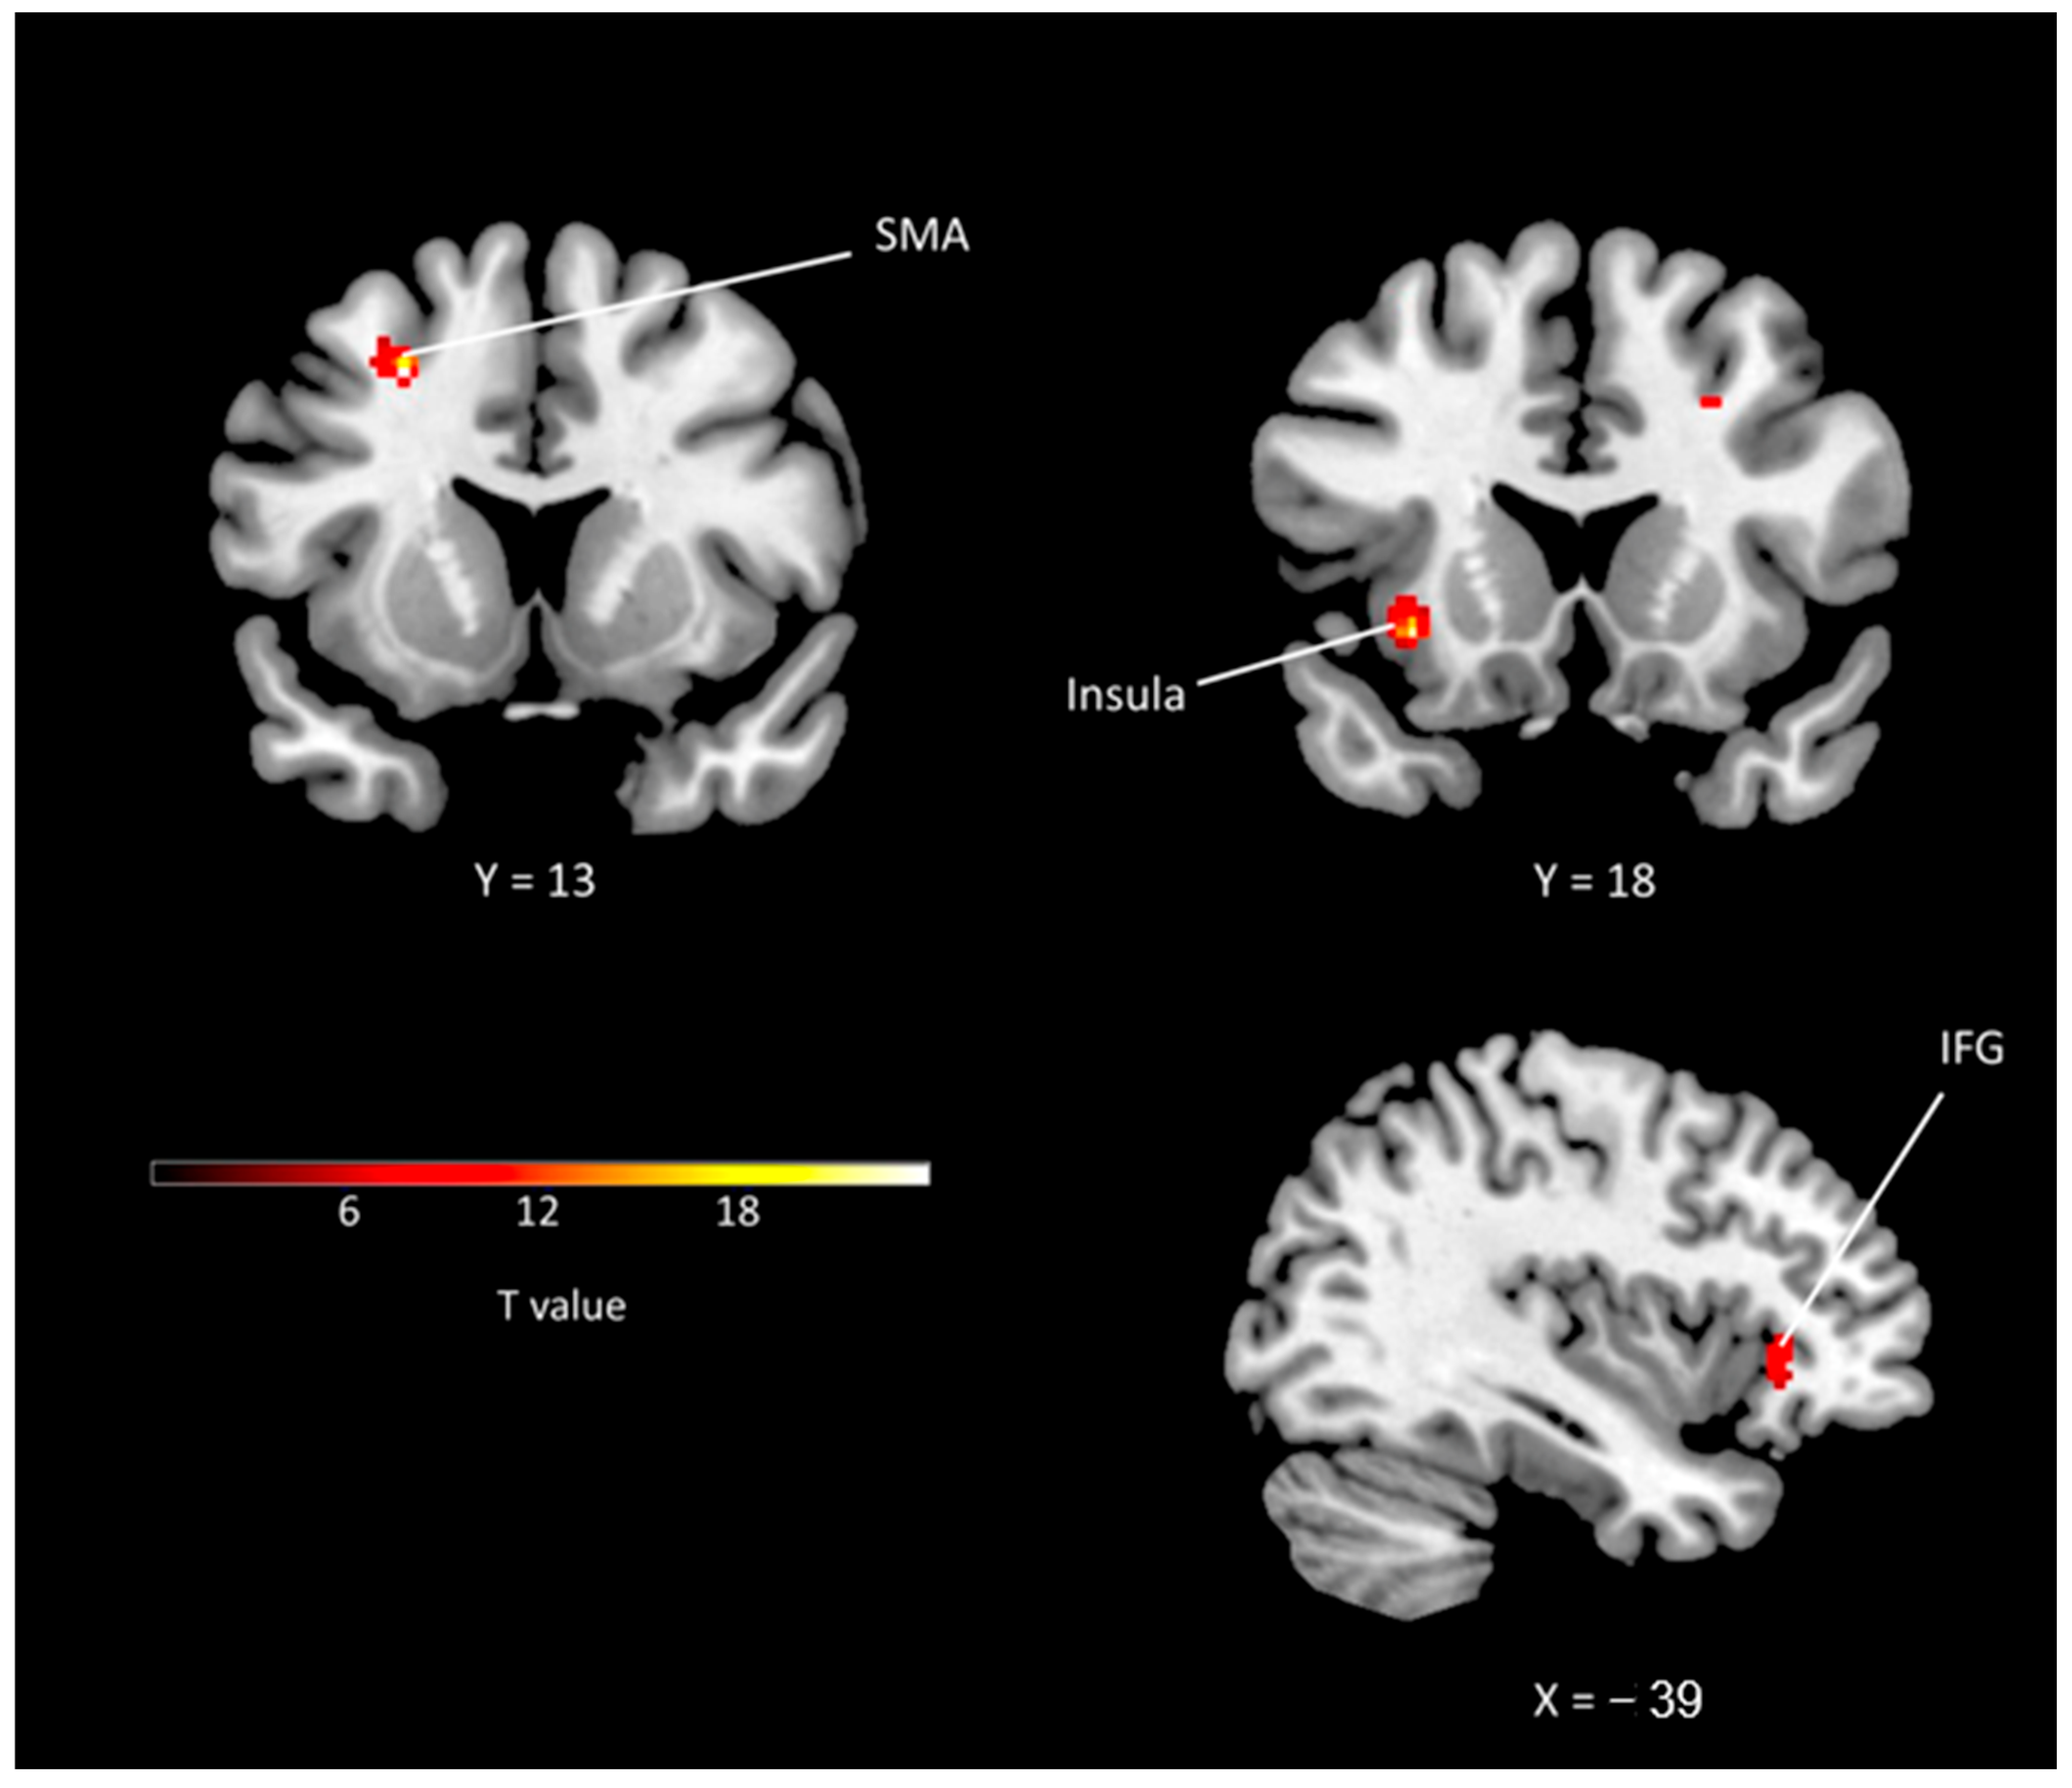

The supplementary motor area demonstrated the highest Z-score (4.70) and the second largest cluster size (50). The insula showed the largest cluster size (113) and the second highest Z-score (4.63). Additionally, the dorsal anterior cingulate (Z-score: 4.51, cluster size: 50), primary motor area (Z-score: 4.50, cluster size: 25), and frontal eye field were among the other regions with significant activation. The anterior prefrontal cortex, cerebellum, inferior frontal cortex, sensory association cortex, thalamus, parahippocampal cortex, caudate, and ventral posterior cingulate were also activated during laughter (Table 1). Figure 2 illustrates the areas of brain activation and the degree of activation.

Figure 2.

Activations revealed by smiling condition. IFG: inferior frontal gyrus; SMA: supplementary motor area.

Prior research has revealed that the supplementary motor area (SMA) is an important region for laughter []. Additionally, humorous cartoons and other stimuli that elicit laughter can modulate SMA activity []. Consistent with previous literature, we observed that the SMA was the region with the highest Z-score in our study. This finding suggests that patients with Ochoa syndrome exhibit brain activation patterns similar to those of healthy individuals. In another study by the same group, striatal reward centers including the putamen, caudate, nucleus accumbens, prefrontal cortices, dorsal anterior cingulate cortex, and SMA were activated during laughter compared with the control condition []. The superior frontal gyrus (Z-score: 4.74), anterior cingulate cortex (Z-score: 3.83), inferior frontal gyrus (Z-score: 3.47), middle frontal gyrus (Z-score: 3.46), and cerebellum (Z-score: 4.63) were the regions activated in the study by Osaka et al. The Z-scores obtained in their study were similar to those observed in patients with Ochoa syndrome in our cohort. Taken together with previous studies in healthy individuals, our findings suggest that the supplementary motor area and the anterior cingulate cortex, two critical regions for the motor control of laughter, are intact and functioning properly in patients with Ochoa syndrome.